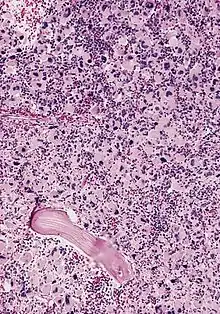

| AML-M7, bone marrow section | |